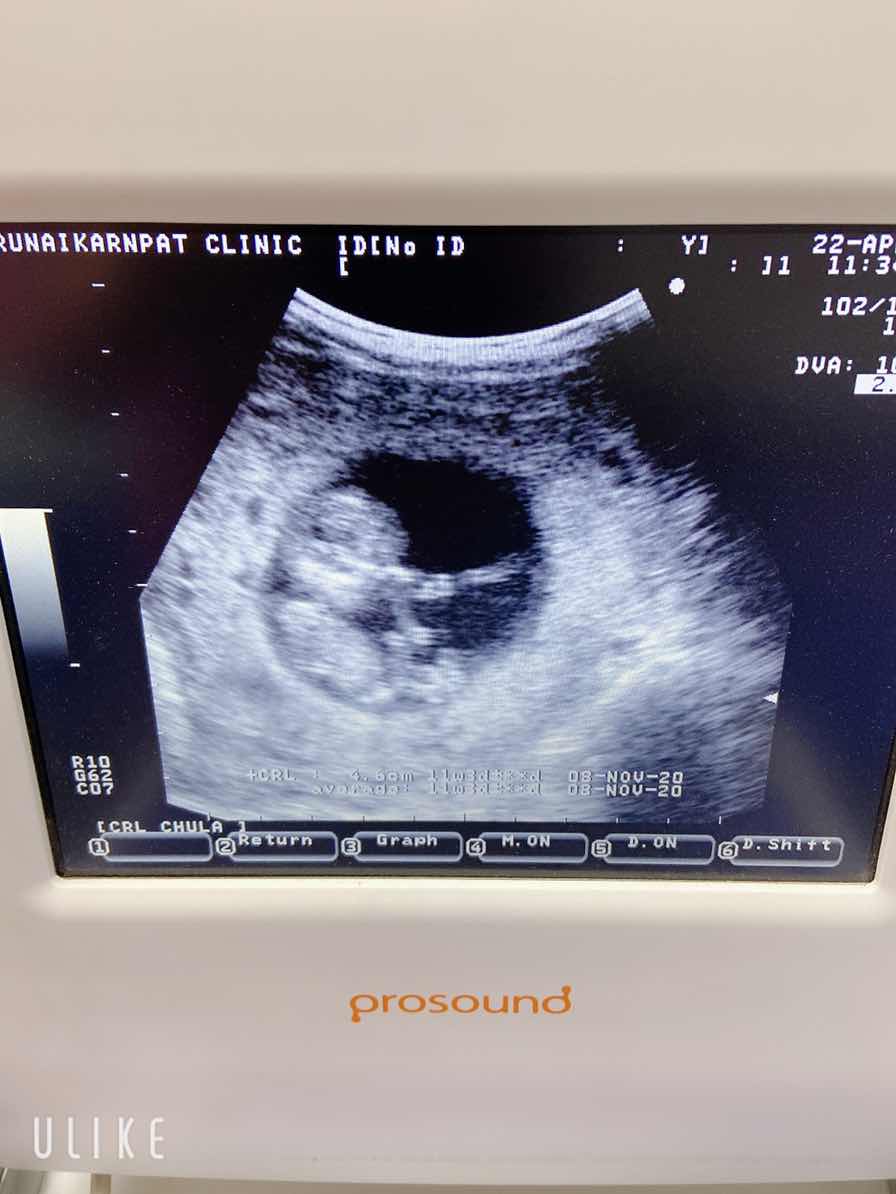

กำหนด9ธันวาคะ